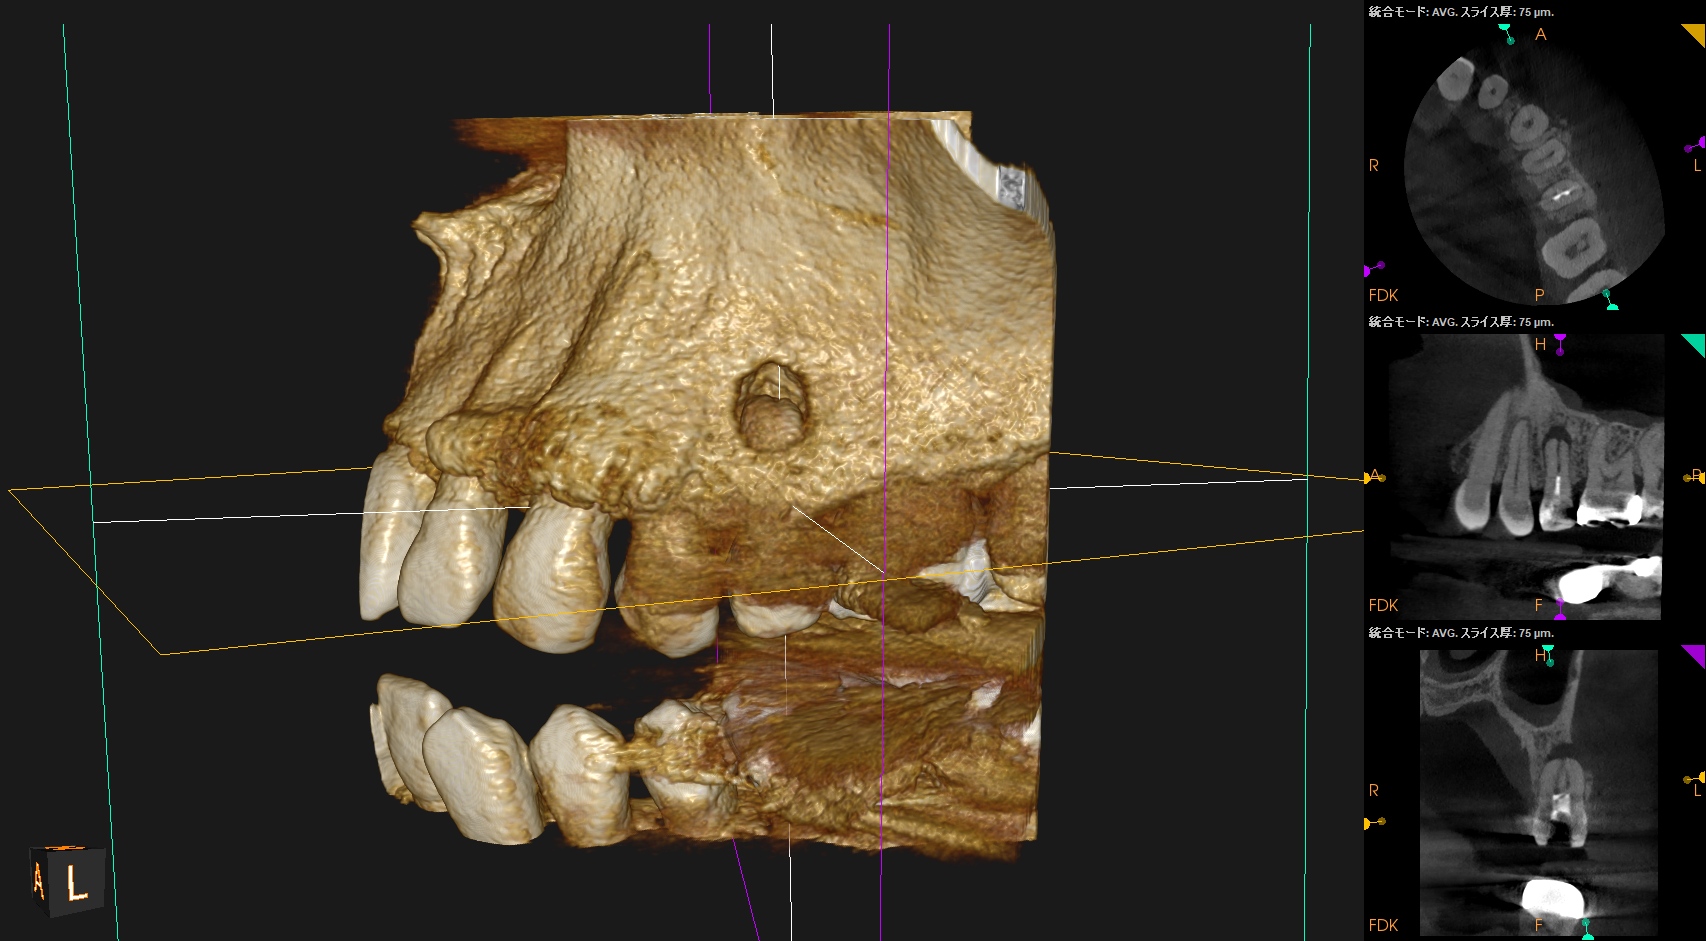

またCBCTを撮影すると、

B

P

歯槽骨は溶けて#13のApexが口腔内に露出しかけている。